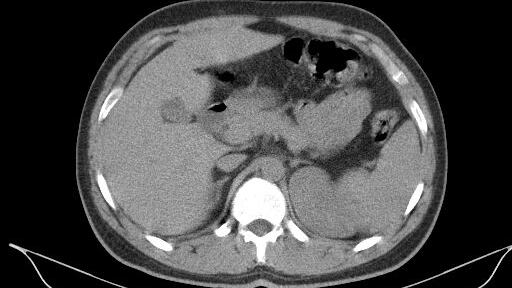

A Florida man had to undergo emergency surgery to address a potentially deadly flesh-eating bacterial infection which developed as a result of him being bitten by a relative, according to a report. Donnie Adams, 52, of Riverview, first developed a small, painful bump on his left thigh two days after he’d been bitten as he attempted to intervene in a tussle between two of his family members. In February, Adams was barely able to walk and had to be taken to the hospital for emergency surgery, where surgeons had to cut out around 70 percent of Adams’ thigh to save his leg, and possibly his life. Doctors at HCA Florida Northside Hospital say they’d never before seen a case of the flesh-eating bacteria—known as necrotizing fasciitis—caused by a human bite. Speaking of the relatives involved in the fracas he broke up, Adams said: “The parties involved are very sorrowful.”